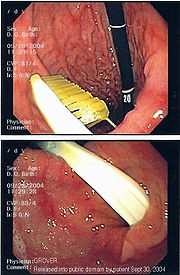

Commonly swallowed objects include coins, buttons, batteries, and small bones (such as fish bones), but can include more complex objects, such as eyeglasses, spoons, and toothbrushes (see image).

Endoscopic retrieval involves the use of a gastroscope or an optic fibre charge-coupled device camera. This instrument is shaped as a long tube, which is inserted through the mouth into the esophagus and stomach to identify the foreign body or bodies. This procedure is typically performed under conscious sedation. Many techniques have been described to remove foreign bodies from the stomach and esophagus. Usually the esophagus is protected with an overtube (a plastic tube of varying length), through which the gastroscope and retrieved objects are passed.

Once the foreign body has been identified with the gastroscope, various devices can be passed through the gastroscope to grasp or manipulate the foreign body. Devices used include forceps, which come in varying shapes, sizes and grips, snares, and oval loops that can be retracted from outside the gastroscope to lasso objects, as well as Roth baskets (mesh nets that can be closed to trap small objects), and magnets placed at the end of the scope or at the end of orogastric tubes. Some techniques have been described that use foley catheters to trap objects, or use two snares to orient foreign bodies.